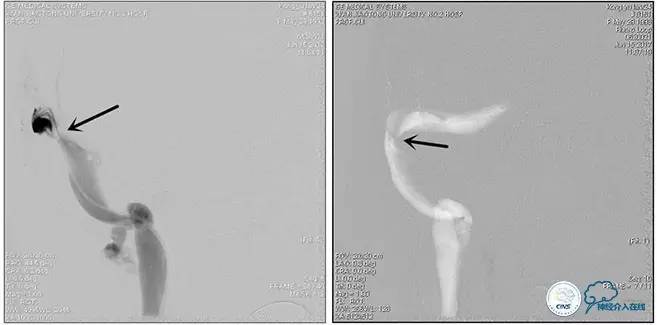

诊疗方案:为挽救视力,确定支架成形术效果,急诊行右侧横窦乙状窦狭窄球囊扩张术(6mm×20mm,Ever Cross )。

术中测压

远端压力:530mmH2O

近端压力:120mmH2O

术中造影

术后造影

狭窄较前有改善